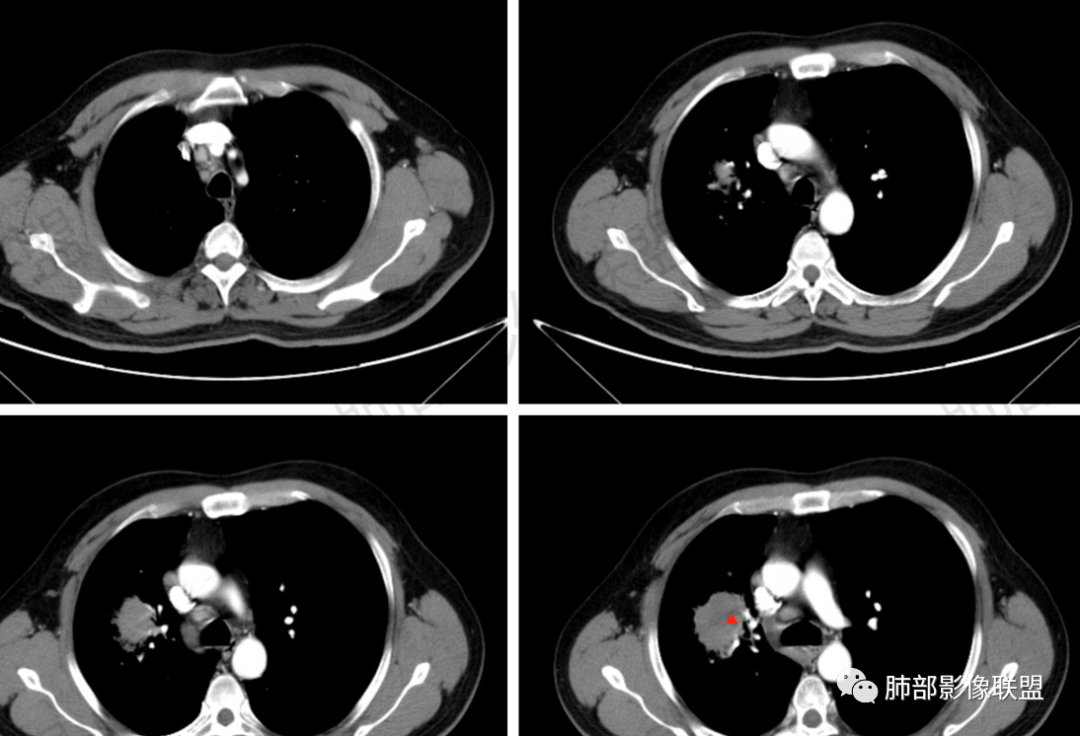

多发树芽,病灶边缘模糊的GGO

环形强化

坏死区几乎是寸草不生

纵隔淋巴结肿大并不明显,就这一个肿大较明显,但仍呈椭圆形,中心少许坏死。

1、坏死区内寸草不生;2、病灶环形强化;3、远端树芽和结节;4、远端不是阻塞性炎症,而是树芽和结节,右肺上叶前后段都有,后段为主,而堵塞的支气管应该是前段;这些树芽的位置不是堵塞支气管的责任区;5、支气管不是突然截断堵塞,而是逐渐狭窄;6、纵隔淋巴结是椭圆形增大,内有坏死,不是肿瘤的圆形饱满;7、支气管周围粘液样坏死,符合仙人掌结核改变;

2、湖泊样坏死:这个病例其实不是湖泊样坏死。湖泊样坏死边界不清,周围有水草样改变;这个病例的坏死更像水库,不是湖泊,坏死区边界清楚,里面寸草不生;

4、纵隔淋巴结肿大:这个病例的淋巴结肿大,不是圆形饱满,而是椭圆形,中间坏死。

水库:是人工的,边缘是石头彻的大坝(环形强化类似大坝),坝缘没草长,边界清楚。

湖泊:是天然的,周围没有环形强化的大坝,是逐渐过渡到强化区的,边缘可有细小血管或者坏死不彻底的肿瘤区。